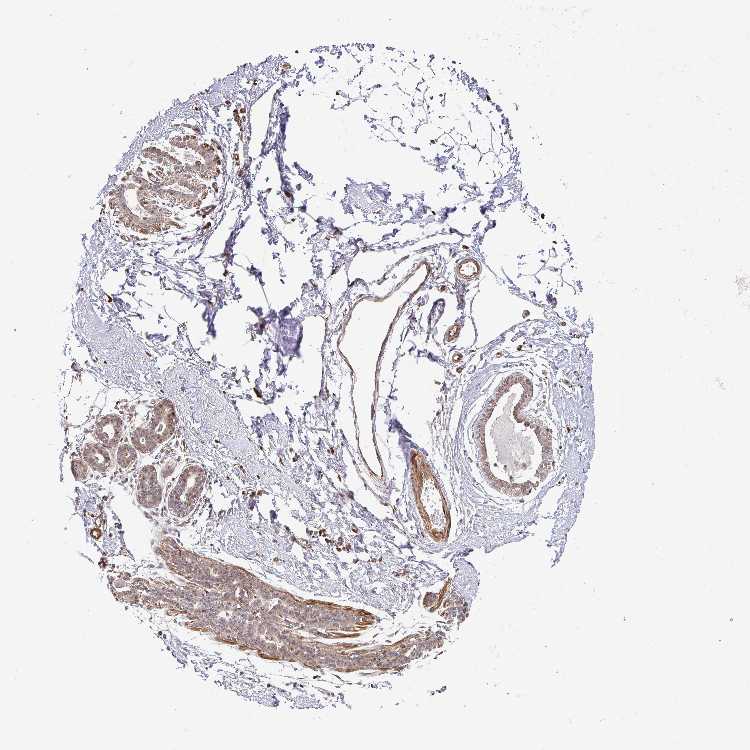

Breast

BREAST - Expression summary

Protein expression

Breasti

On the top, protein expression in current human tissue, based on all annotated cell types, is reported with the units not detected (n), low (l), medium (m) and high (h). Underneath, protein expression in each annotated cell type are reported using the same units.

Protein expression data is based on knowledge-based annotation. For genes where more than one antibody has been used, a collective score is set.

If knowledge-based annotation could not be performed for a gene, no data is displayed here. View antibody staining data further down this page.

Adipocytes: Not detected

Glandular cells: Medium

Myoepithelial cells: Medium

BREAST - Antibody stainingi

Antibody staining in the annotated cell types in the current human tissue is reported as not detected, low, medium, or high, based on conventional immunohistochemistry profiling in selected tissues. This score is based on the combination of the staining intensity and fraction of stained cells.

Each image is clickable and will lead to virtual microscopy that enables deeper exploration of all samples and also displays staining intensity scores, fraction scores and subcellular localization as well as patient and tissue information for each sample.

Antibody HPA037890

Adipocytes Not detected

Glandular cells Medium

Myoepithelial cells Medium